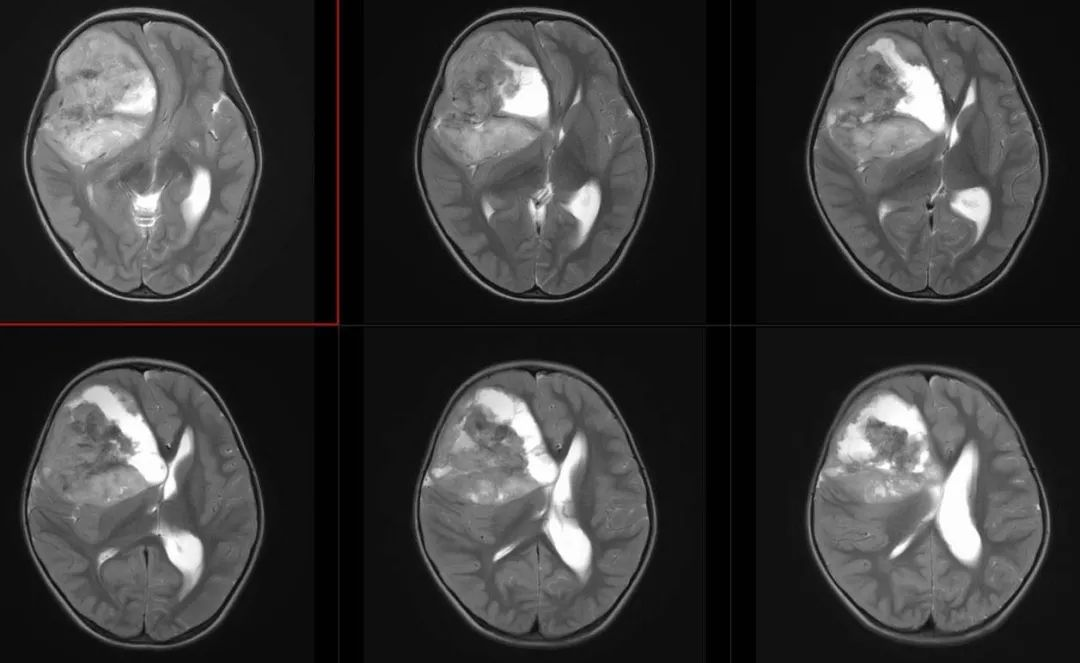

术前影像

术前FLAIR

术前T2轴位